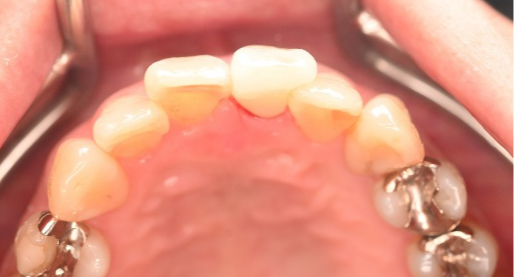

女性Mさん 40代(オールセラミック冠)

上の前歯をきれいにしたい。

治療内容

前歯4本を根管治療をし、オールセラミック冠を被せました。

所感

右の1本は、被せ物をしていましたが、すり減り形が変わり、変色もしていました。他の3本はすでに神経がない状態で、詰め物をしていましたが、詰め物及び歯自体も変色し、詰め物と自分の歯の境目のところからむし歯になっていました。治療後「きれいになって嬉しいです。治療して本当に良かったです。」と、とても喜んでくださいました。

オールセラミック冠4本:¥104,500×4本=¥418,000(税込)

Before

After